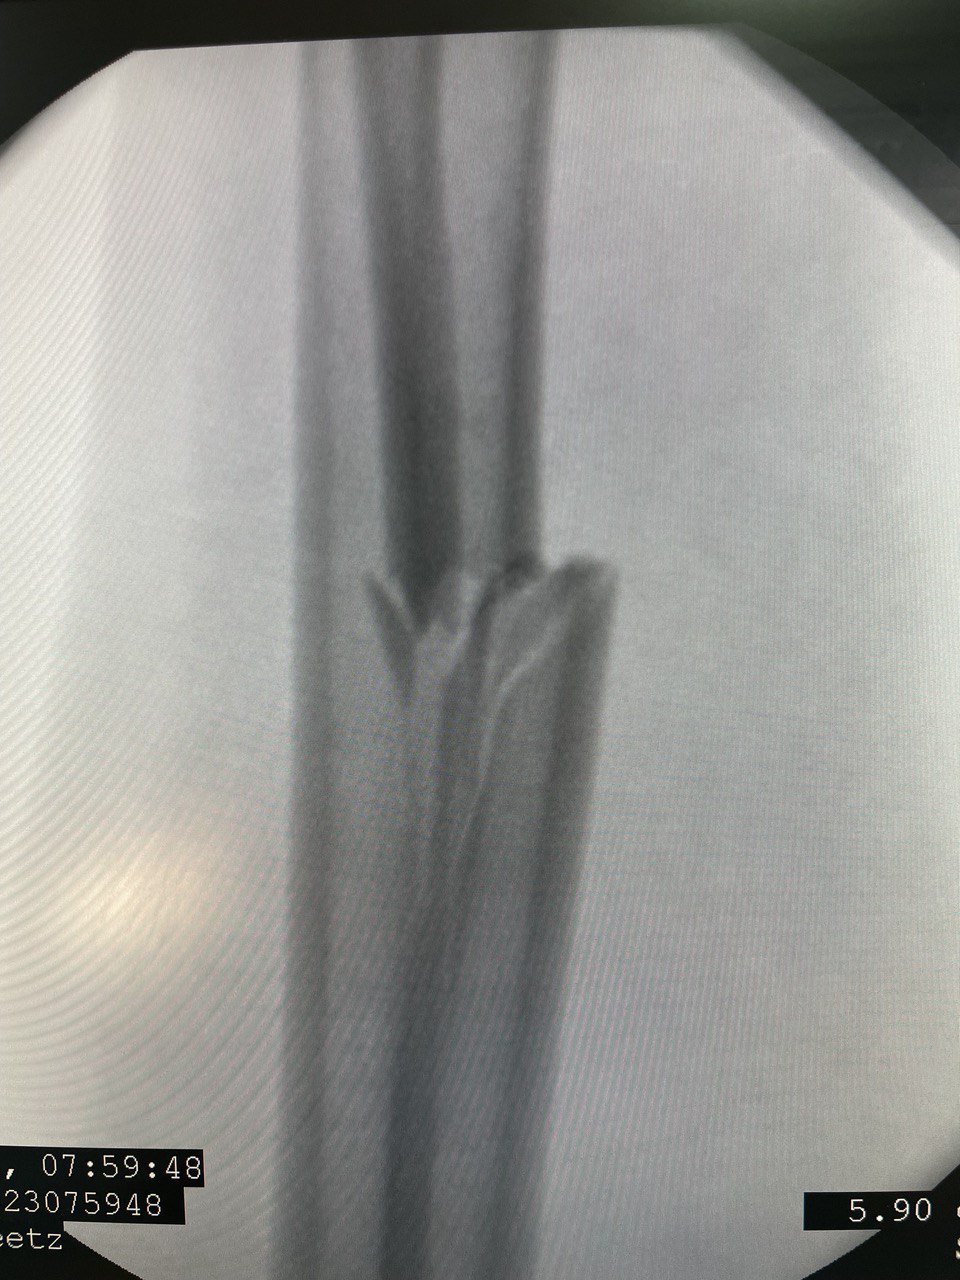

Клинический случай: перелом диафиза лучевой кости

Клинический случай с повреждением диафиза лучевой кости и последовательным контролем состояния.